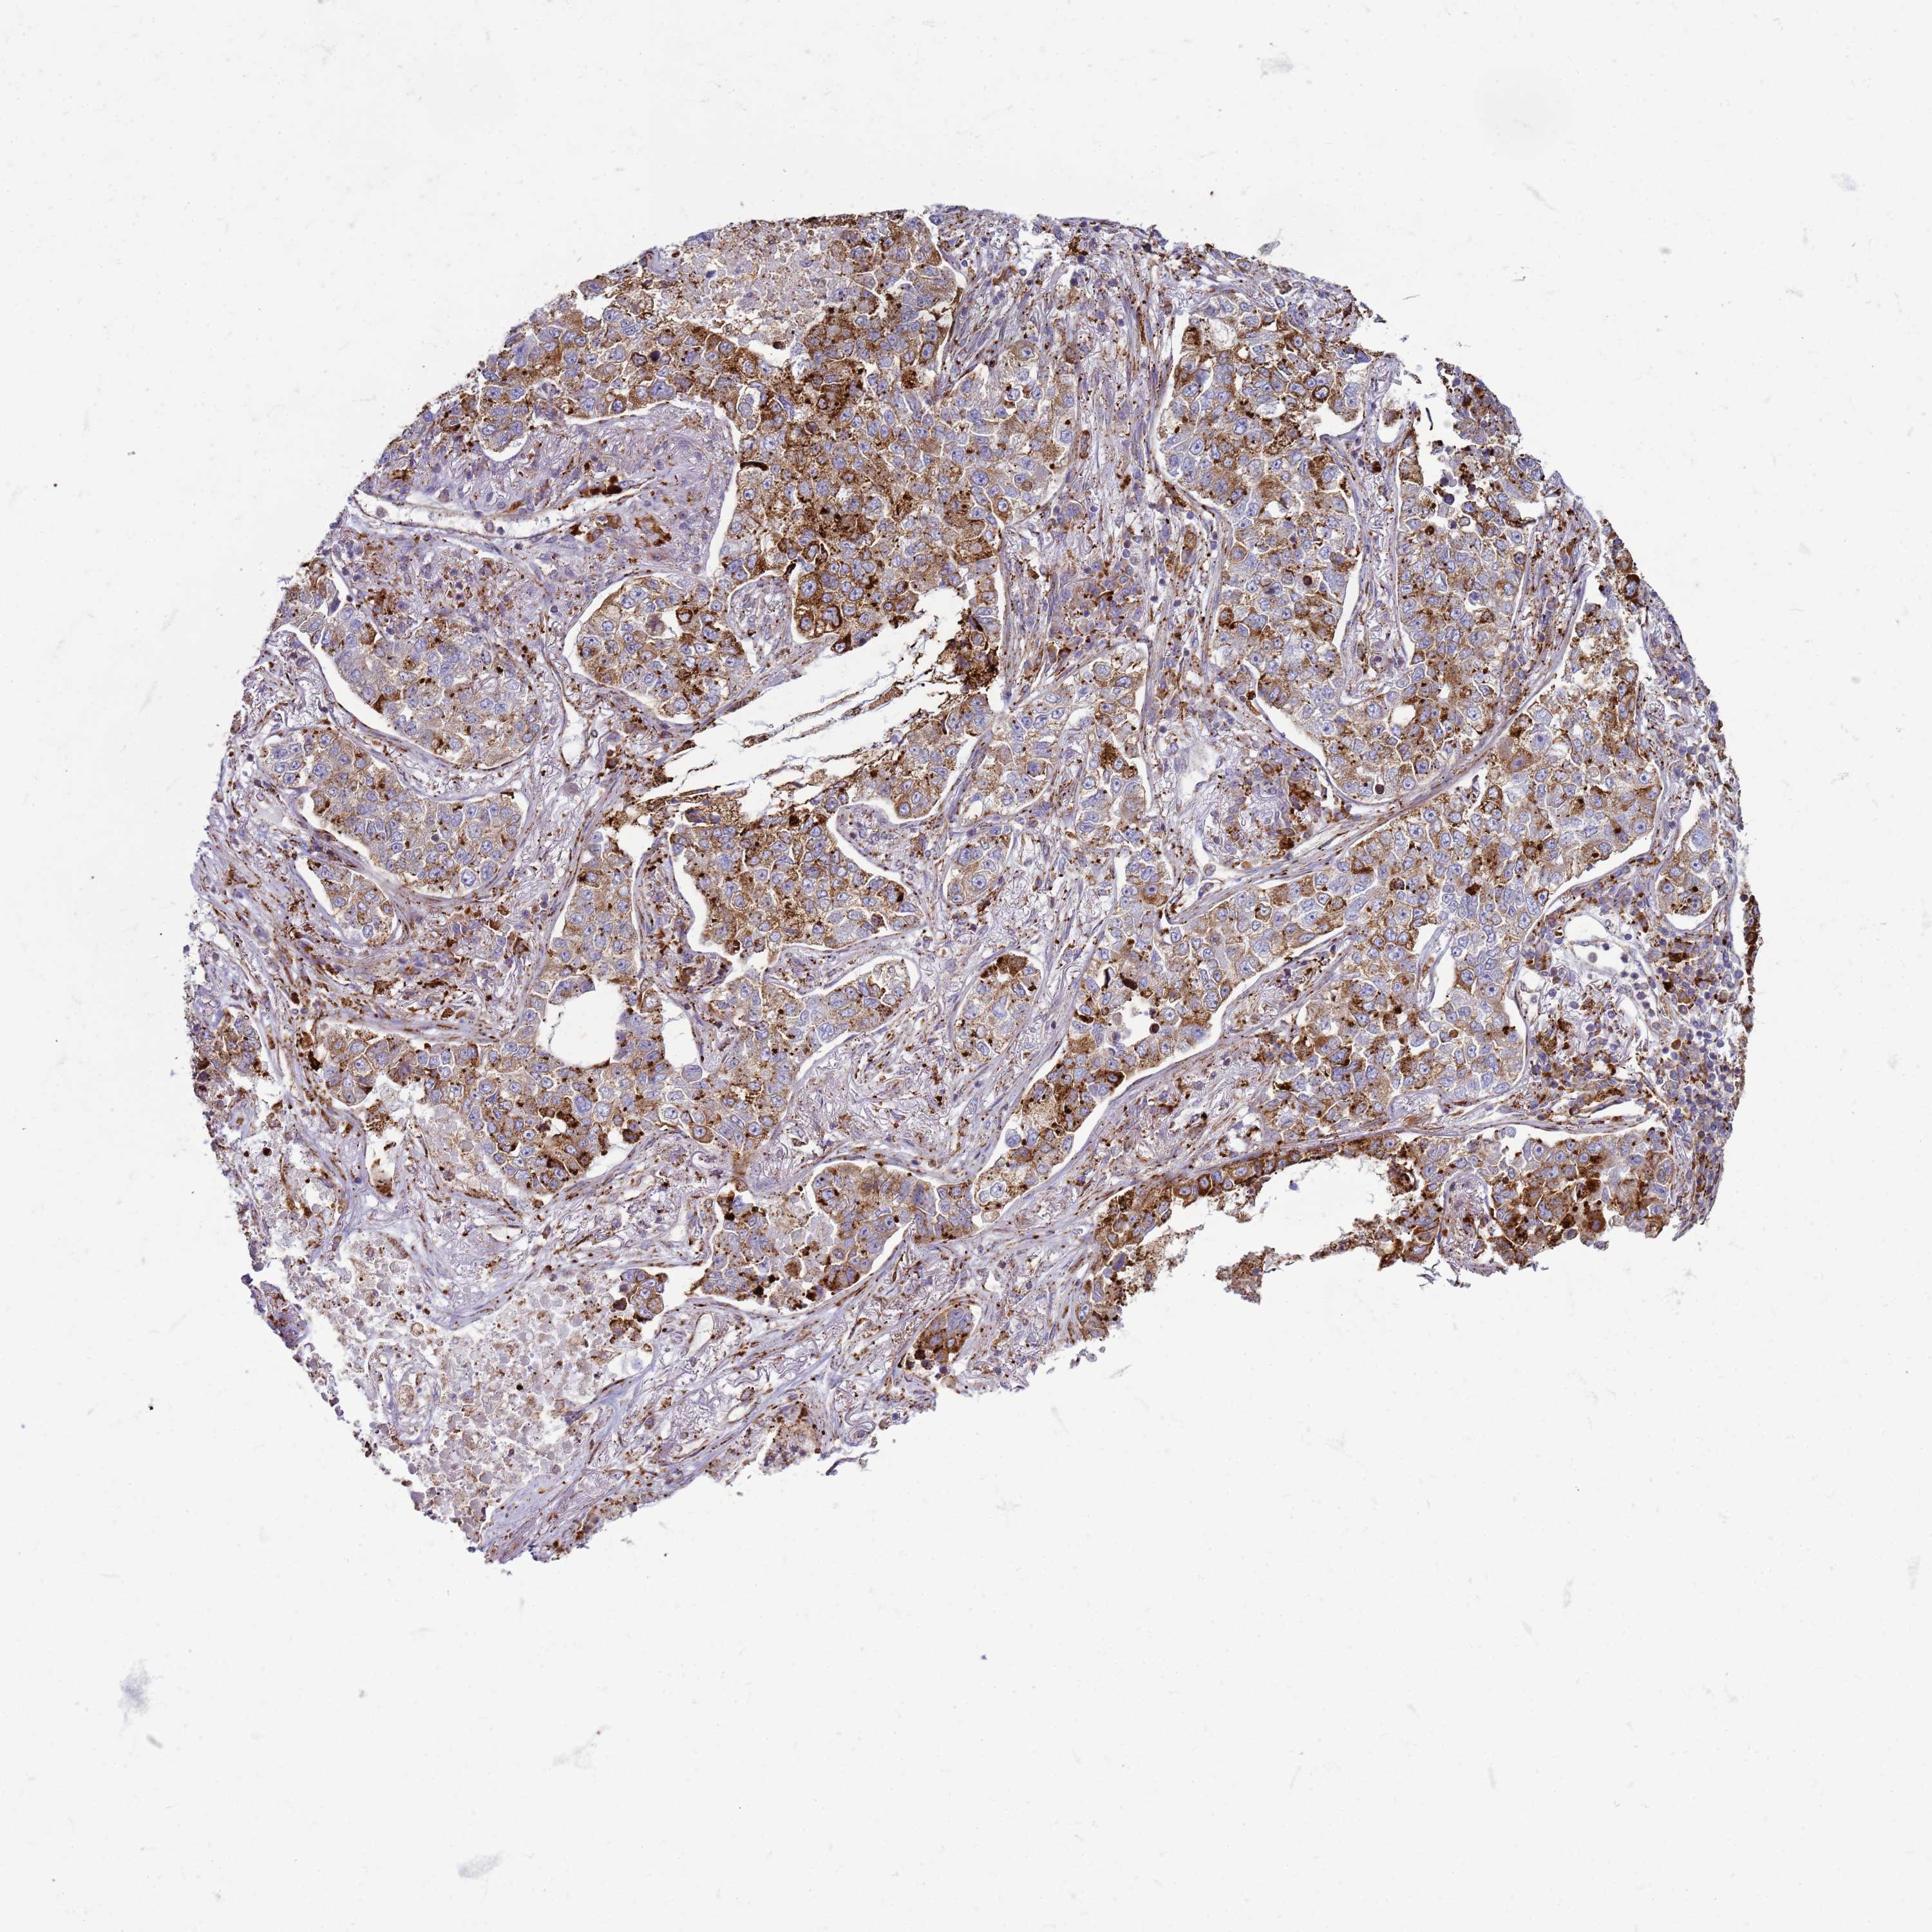

LUNG ADENOCARCINOMA (TCGA) - Interactive survival scatter ploti

The Survival Scatter plot shows the clinical status (i.e. dead or alive) for all individuals in the patient cohort, based on the same data that underlies the corresponding Kaplan-Meier plots. Patients that are alive at last time for follow-up are shown in blue and patients who have died during the study are shown in red.

The x-axis shows the expression levels (FPKM) of the investigated gene in the tumor tissue at the time of diagnosis. The y-axis shows the follow-up time after diagnosis (years). Both axes are complimented with kernel density curves demonstrating the data density over the axes. The top density plot shows the expression levels (FPKM) distribution among dead (red) and alive patients (blue). The right density plot shows the data density of the survived years of dead patients with high and low expression levels respectively, stratified using the cutoff indicated by the vertical dashed line through the Survival Scatter plot. This cutoff is automatically defined based on the FPKM cutoff that minimizes the p-score. The cutoff can be changed by dragging the vertical line or by entering a cutoff value in the square labeled "Current cut-off".

Under the Survival Scatter plot the p-score landscape (black curve; left axis) is shown together with dead median separation (red curve; right axis). Dead median separation is the difference in median mRNA expression between patients who have died with high and low expression, respectively. It is calculated as follows: median FPKM expression of dead patients with high expression - median FPKM expression of dead patients with low expression. This is intended to aid the user in visually exploring custom cutoffs and the associated p-scores and dead median separation.

Individual patient data is displayed and can be filtered by clicking on one or more of the category buttons on the top of the page. Categories describing expression level and patient information include: high, low, alive, dead, female, male and tumor stages. The scale of the x-axis can be toggled between linear and log-scale by clicking on the "x log" button. Mouse-over function shows TCGA ID, patient information and mRNA expression (FPKM) for each patient.

& Survival analysisi

Kaplan-Meier plots summarize results from analysis of correlation between mRNA expression level and patient survival. Patients were divided based on level of expression into one of the two groups "low" (under cut off) or "high" (over cut off). X-axis shows time for survival (years) and y-axis shows the probability of survival, where 1.0 corresponds to 100 percent.

PDK3 is not prognostic in Lung Adenocarcinoma (TCGA)

Best expression cut offi

Based on the FPKM value of each gene, patients were classified into two groups and association between prognosis (survival) and gene expression (FPKM) was examined. The best expression cut-off refers the FPKM value that yields maximal difference with regard to survival between the two groups at the lowest log-rank P-value. Best expression cut-off was selected based on survival analysis .

When clicking on this number, the vertical dashed line indicating cut-off, the interactive survival plot, and the Kaplan-Meier curve will be adjusted to show results based on the best expression cut-off.

: 6.17

P scorei

Log-rank P value for Kaplan-Meier plot showing results from analysis of correlation between mRNA expression level and patient survival.

N/A

5-year survival highi

5-year survival for patients with higher expression than the expression cutoff.

For melanoma and glioma, 3-year survival is shown.

5-year survival lowi

5-year survival for patients with lower expression than the expression cutoff.

TCGA RNA samplesi

RNA-seq data is reported as average FPKM (number Fragments Per Kilobase of exon per Million reads), generated by the The Cancer Genome Atlas (TCGA) .

Normal distribution across the dataset is visualized with box plots, shown as median and 25th and 75th percentiles. Points are displayed as outliers if they are above or below 1.5 times the interquartile range. FPKM values of the individual samples are presented next to the box plot.

Average pTPM 5.7

Number of samples 497